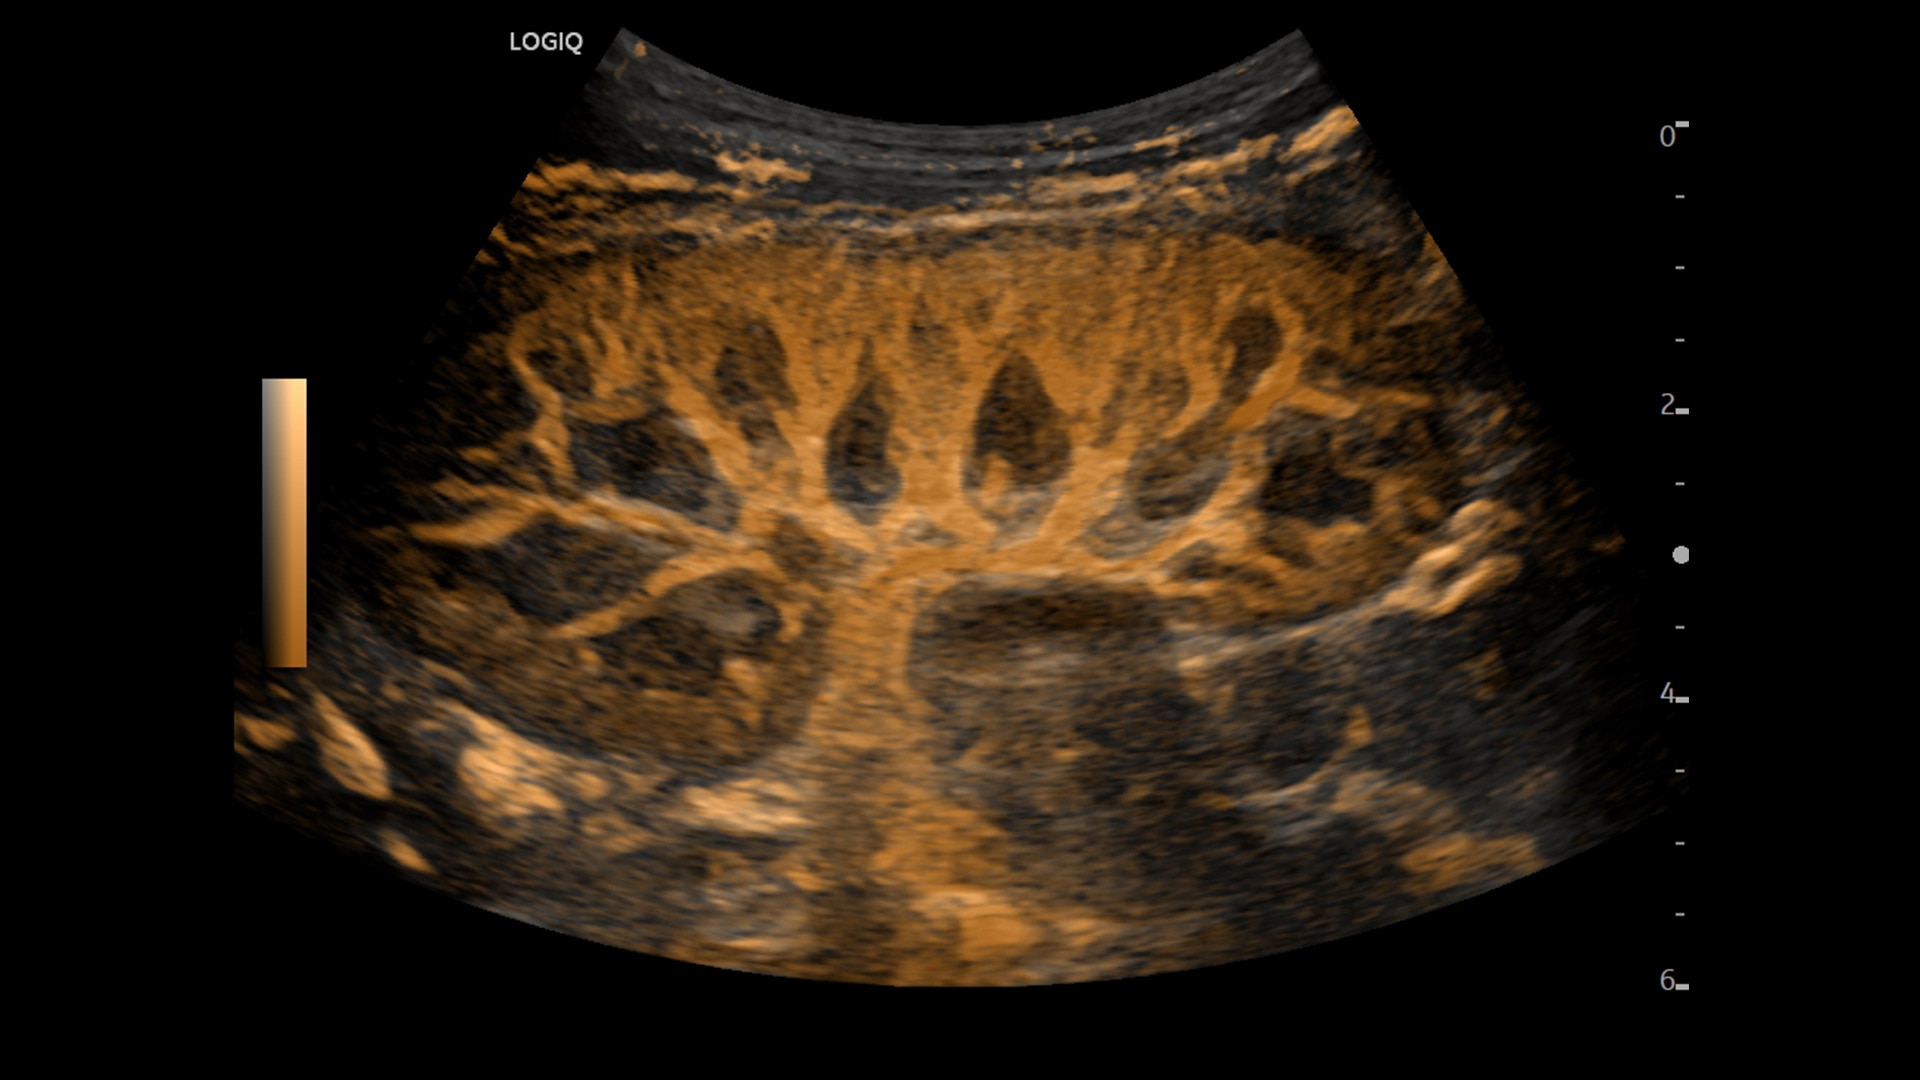

Strength and power to enhance clinical capabilities and deliver exceptional image quality